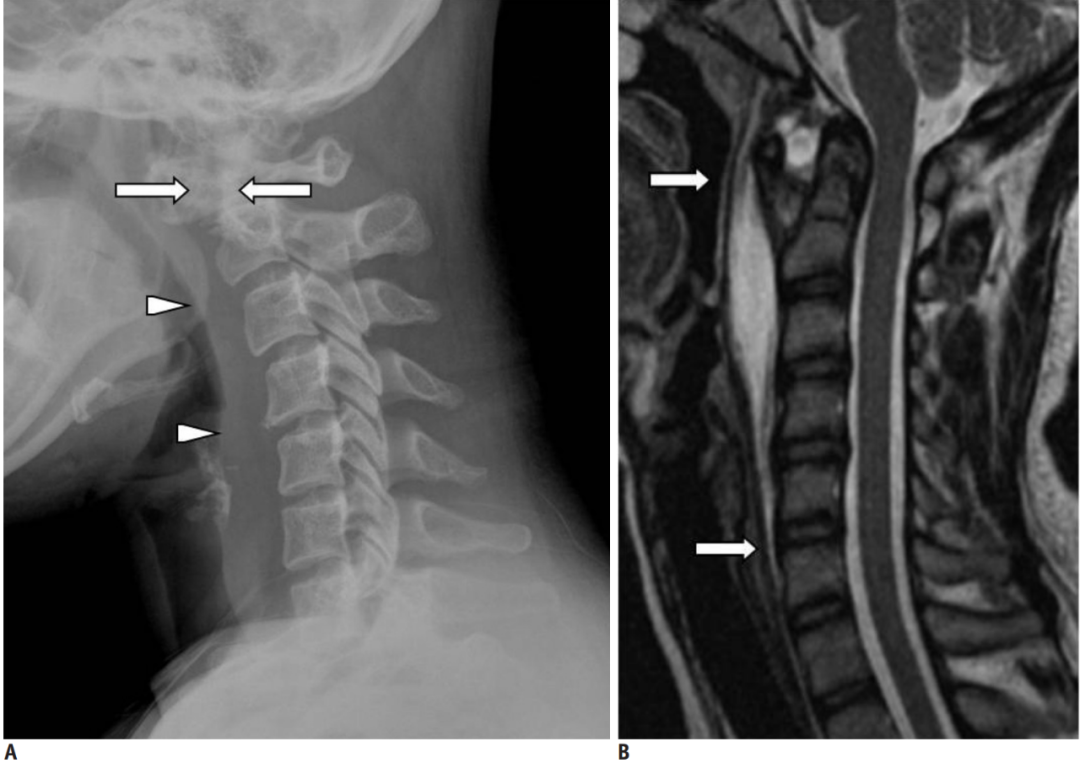

图:患者8岁,女孩,因严重颈部疼痛、活动受限伴左上肢无力、麻木不适2天就诊。既往有锁骨骨折、额部软组织挫伤病史。查体:颈椎活动受限,左上肢肌力正常,但感觉减退。白细胞、血沉、CRP升高。颈椎侧位片和CT平扫提示C6-7椎间盘钙化(粗箭头)和后纵韧带骨化(细箭头),颈椎MRI提示C6-7水平脊髓明显受压。给予颈椎制动、枕颌带2.5kg颈椎牵引2周。随后,颈托固定1个月。2年后随访复查颈椎CT如下图,同时上述症状完全缓解。

图:2年后复查CT示C6-7钙化的椎间盘和后纵韧带骨化都消失了